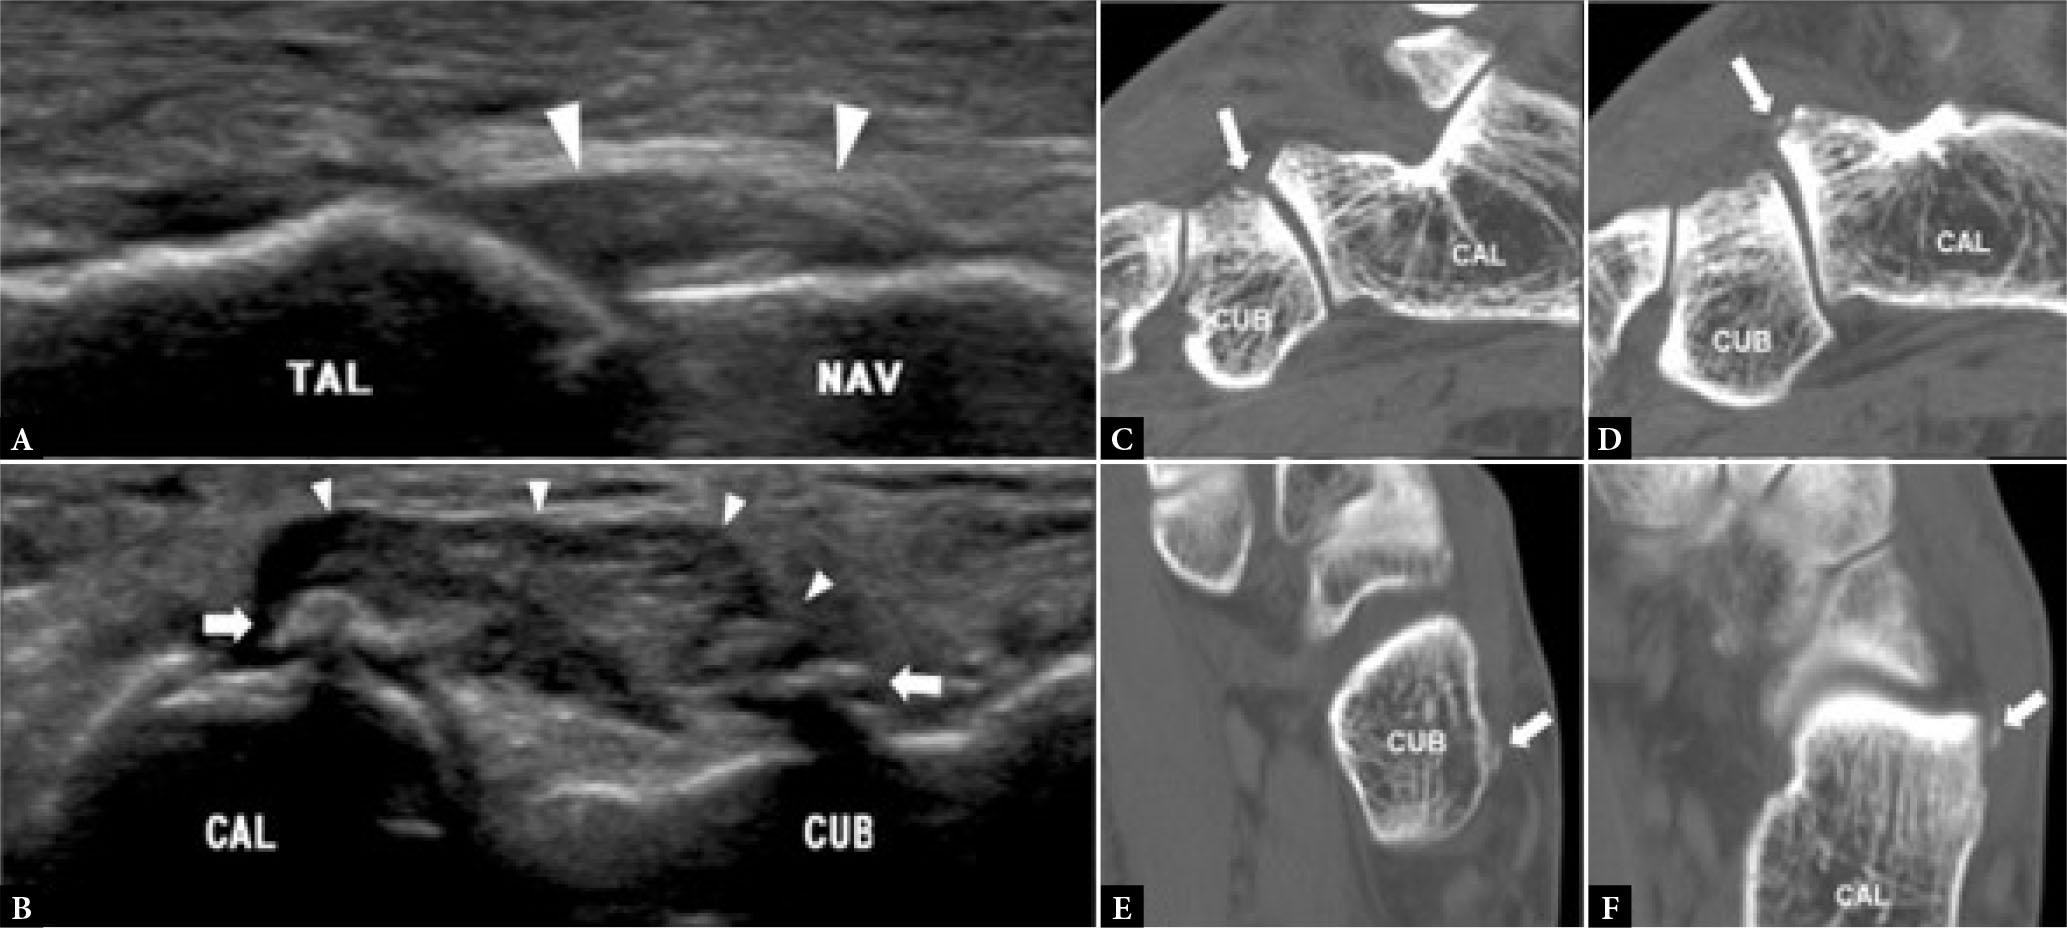

The plantar plate is the most frequently injured component of the 1st MTP joint though other supporting structures can also be torn either in isolation or in conjunction with a plantar plate tear. Plantar plate injury may be acute from traumatic hyperextension or chronic. The relative prevalence of acute or chronic tears seen is largely dependent on the referral population. Chronic tears occur in degenerative attenuated plantar plates from repetitive overload (Fig. 12). On MRI, degenerated plantar plates will tend to have intermediate rather than low signal intensity on all pulse sequences(11). Partial tears are more common than complete tears. If complete tears are accompanied by tearing of the supporting sesamoid ligaments, proximal migration of one or both sesamoid bones may occur. Unlike plantar plate tears of the lesser MTP joints, 1st MTP joint plantar plate tears tend not to induce exuberant reactive capsular/pericapsular fibrosis.

Fig. 12.

58-year-old female with forefoot pain. T2W fat-suppressed sagittal images though the A. medial, B. mid-line, and C. lateral aspects of the big toe. At the 1st MTP joint, the Index medial (##) and lateral (#) metatarso-sesamoid ligaments are intact with a complete tear of the attenuated plantar plate (arrow). At the interphalangeal joint, there is a degenerative thickened plantar plate (arrowhead) with an overlying mildly distended adventitial bursa (open arrow). D. T2W fat-suppressed coronal image also shows a tear of the inter-sesamoid ligament (arrow). MT1, 1st metatarsal bone, PP, proximal phalanx